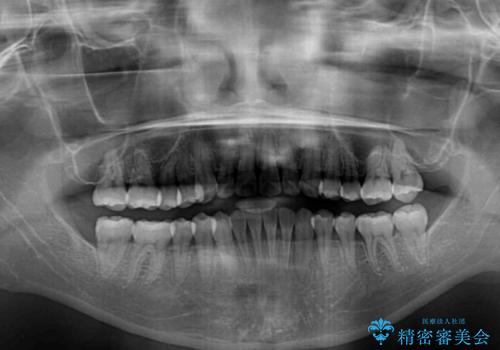

- 治療期間

- 1年10ヶ月

オープンバイトは容易に後戻りを起こすため、少しでも後戻りリスクを軽減するために舌癖改善のトレーニングをしっかりと行っていただきました。